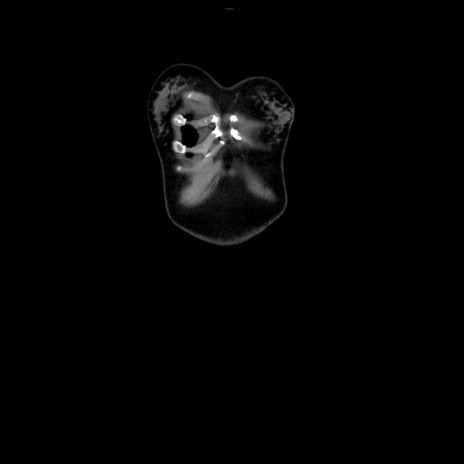

症例39(冠状断像)

【症例】40歳代女性

【主訴】上下腹部痛

【現病歴】2日目から下腹部痛あり。夜間は痛みで眠れなかった。昨日より上腹部痛と下痢が出現。臥位で痛みは軽快したため、休んでいた。本日になって臥位でも立位でも痛みが強くなってきたため救急要請。

【既往歴】子宮内膜症

【身体所見】部:平坦・軟、左上下腹部に圧痛あり、反跳痛あり。

【データ】WBC 21800、CRP 26.78

CT